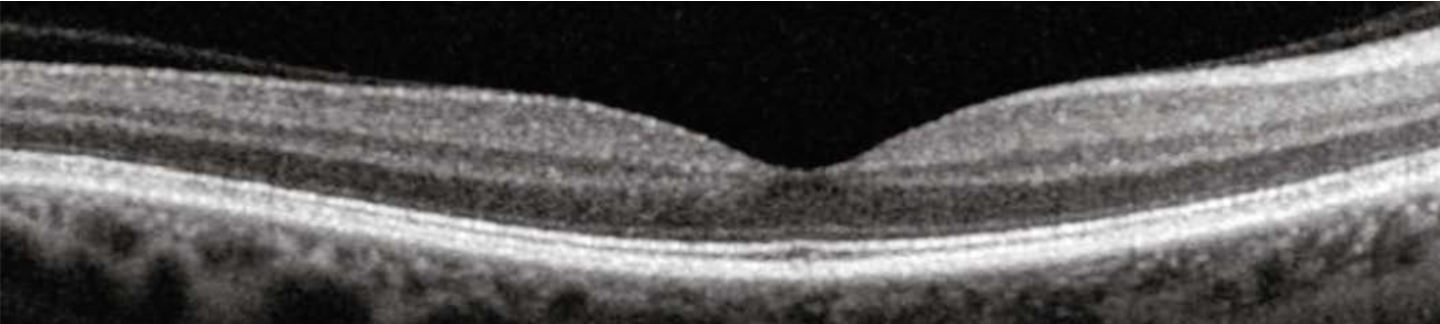

Zur umfassenden Untersuchung und Abklärung Ihrer Augen und Ihrer Wahrnehmung stehen der Optometristin und dem Optometristen eine Vielzahl von Methoden und Untersuchungsgeräten zur Verfügung. Diese werden spezifisch und nach Bedarf eingesetzt. Die folgenden Beispiele zeigen eine kleine Auswahl aus den zahlreichen Möglichkeiten, alle auf dem höchsten technologischen Standard: